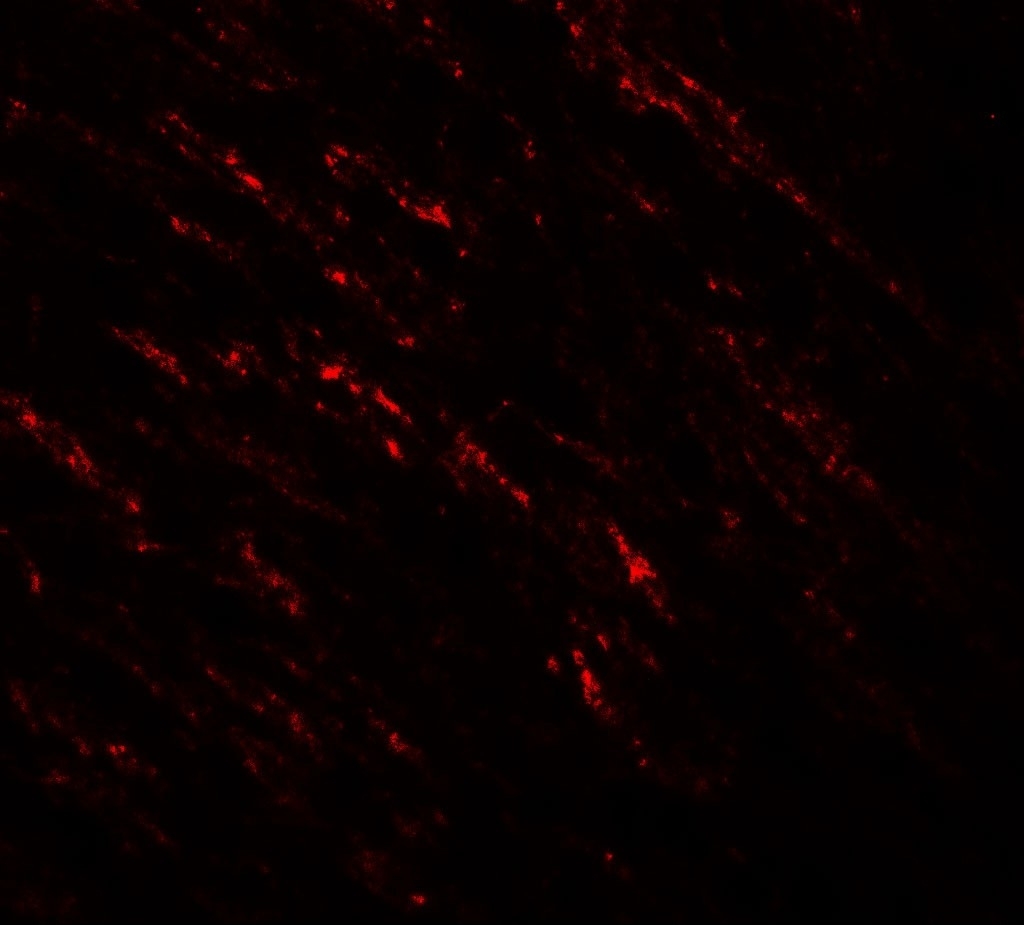

Supportive validation

- Submitted by

- Arigo (provider)

- Main image

- Experimental details

- Immunofluorescence: human small intestine tissue stained with ARG54673 anti-B-raf antibody at 20 µg/ml.